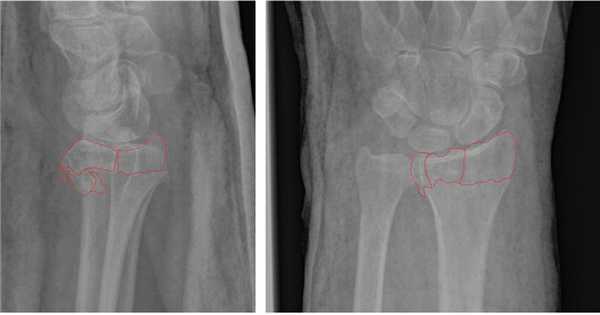

Несмотря на это многие травматологи продолжают лечить такие переломы методом гипсовой иммобилизации. В конечном итоге перелом срастается с грубым смещением, суставная поверхность оказывается развёрнута в тыльную и лучевую сторону.

Формируется грубый артроз лучезапястного сустава. Клинически это проявляется визуально деформацией в области лучезапястного сустава, ограничением амплитуды движений, болью при физической нагрузке.

По этой причине в нашей клинике мы предпочитаем лечить такие типы переломов оперативно. Для фиксации данного типа повреждений предпочтительно использовать пластины с угловой стабильностью с дистальным расположением винтов, которые можно ввести субхондрально, ближе к суставной поверхности. В своей практике мы используем пластины фирмы Synthes - 2.4mm Variable Angle LCP® Volar Rim Distal Radius System.